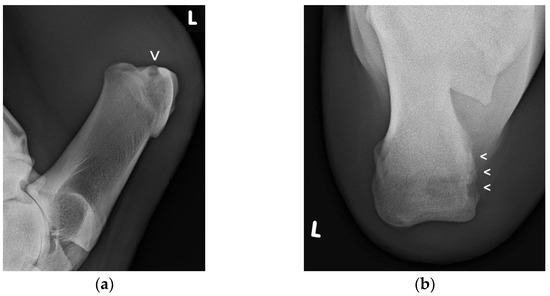

Radiographic examination (Figure 3a,b) was performed in 19 patients (65.5%): in fifteen cattle on the day of admission, in three cattle later on during hospitalization, and in one patient, radiographs were made at admission and again later. The various radiographic findings are shown in Table 1.

Figure 3. Lateromedial (a) and proximodistal radiographic views (b) of the left CT region of this cow showing an extended radiolucent zone (small arrow/s) at the proximomedial aspect of the CT, indicating bone osteolysis (Figure 3a,b courtesy of the Clinical Unit of Diagnostic Imaging, Vetmeduni Vienna, Austria).